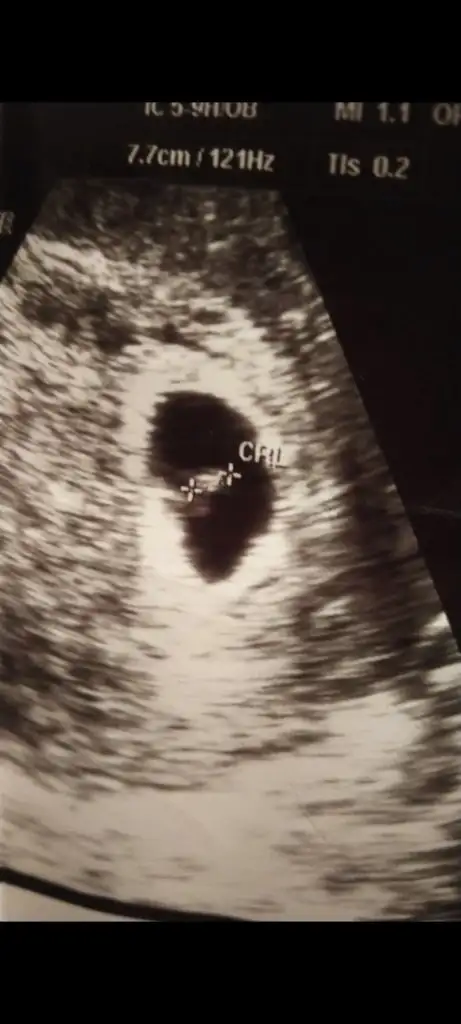

Sizinki erkek olabilir6+5 karından Ultrason bana da yorum yaparmısınEki Görüntüle 3148394

5 ve 14. haftaya kadar olan ultrason fotolarınızı paylaşın. Vajinadan mı yoksa karından mı çekildiğini ve kaç haftalık olduğunu da mutlaka belirtin.

Burdada erkek gibi duruyor bende hamildyim 7haftalij olcak tüm ultrasonlara baktım meraktan benimkine erkek çıkıyor hakkımızda hayırlısı Rabbim gonlumuzdekini gerçekleştirsin inşallahBuda 7 haftalik karindan